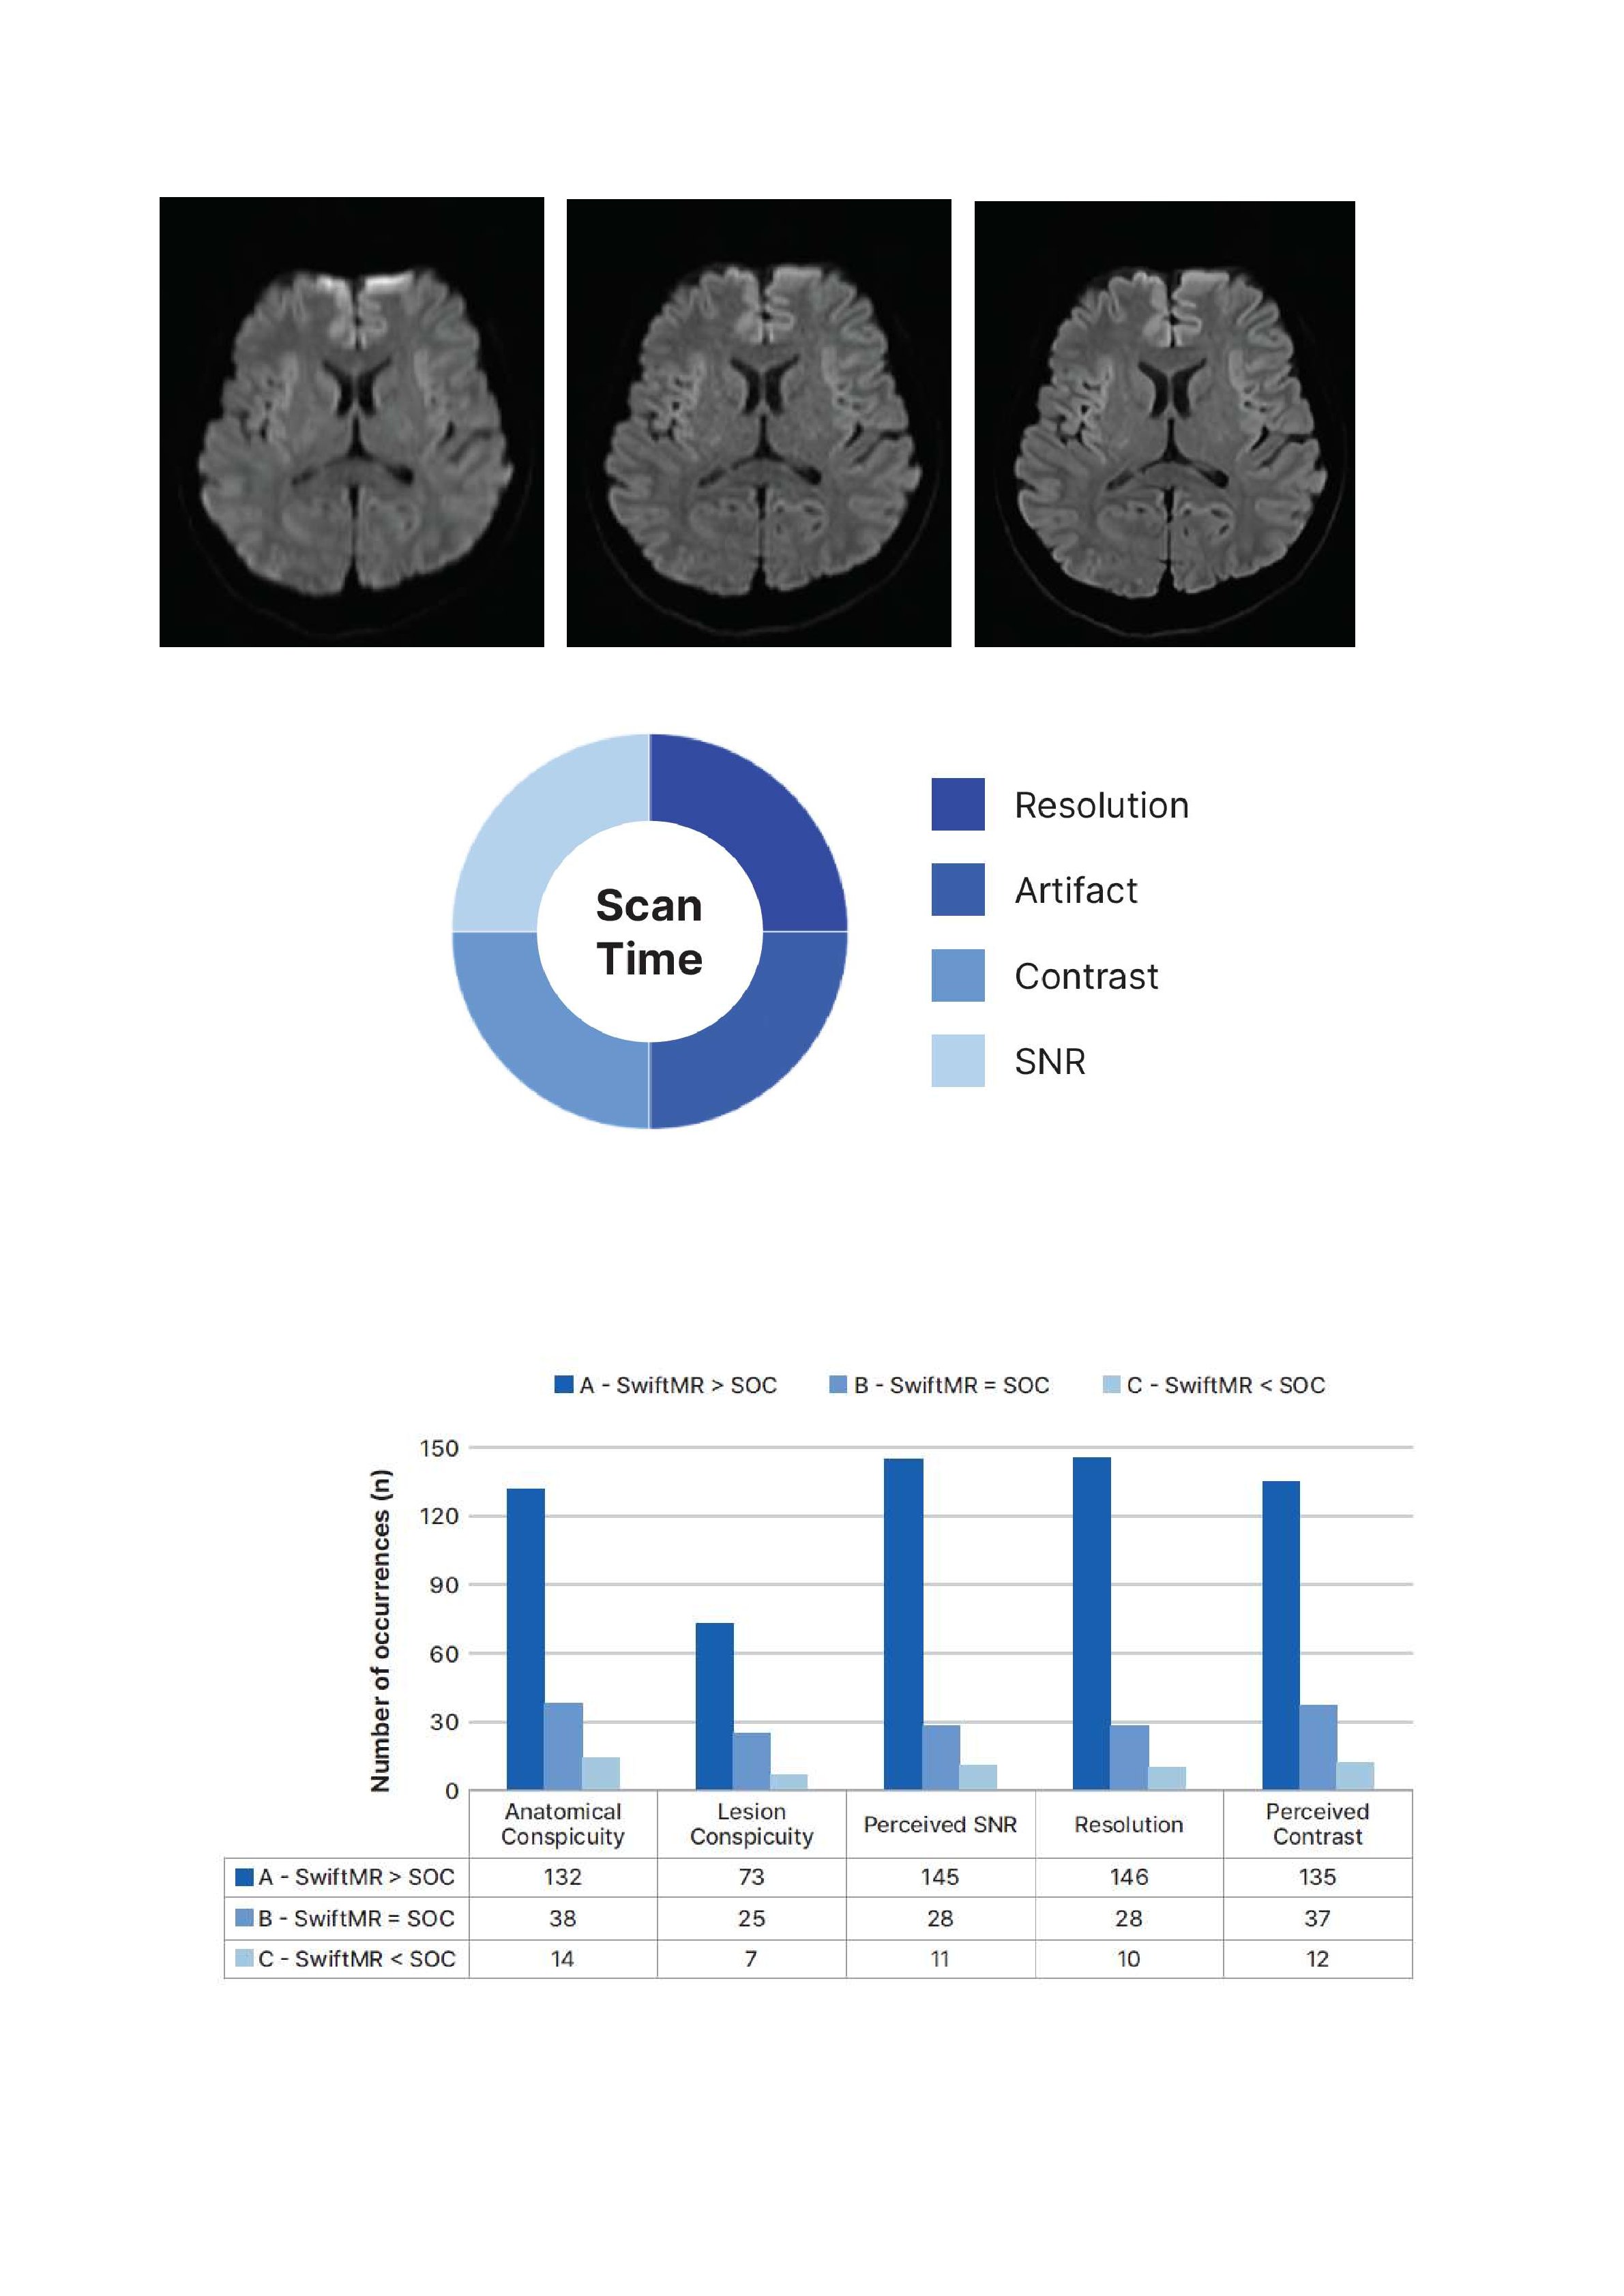

A partire da una richiesta di prova del sistema SwiftMRTM del Dipartimento Interaziendale ad Attività integrata di Diagnostica per Immagini, l’Ingegneria Clinica ha proposto una revisione della letteratura disponibile per ampliare il numero di casi studiati, beneficiare delle esperienze e delle conclusioni espresse, adottare una ipotesi di lavoro e di protocollo per alcuni distretti anatomici e massimizzare l’utilità del sistema.

Dividendo per distretto anatomico e tecnologia le conclusioni, si ricerca la definizione del miglior protocollo, inteso come rapporto fra guadagno di tempo e di qualità dell’immagine, da applicare in modo sistematico alla produzione di immagini diagnostiche con il massimo vantaggio.